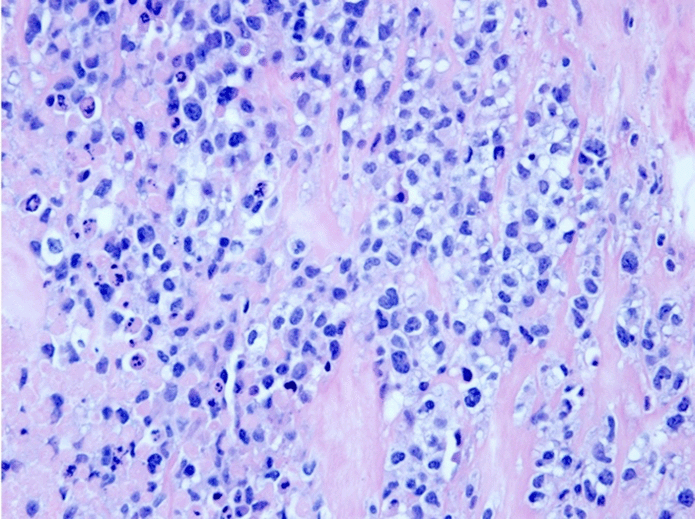

On microscopic examination of the right capsule (Figure 3), there was a thick layer of fibrinonecrotic material on the luminal side of the capsule, corresponding to the gross caseous material. Within the fibrin was extensive tumor necrosis and ghosts of lymphoma cells, with small pockets of preserved large lymphoma cells. Immunohistochemistry showed the neoplastic cells to be positive for CD30, CD4, epithelial membrane antigen, TIA-1, and CD43. The left implant capsule had only reactive changes and no morphologic evidence of lymphoma.

Figure 3B.

Higher magnification image (40x) showing numerous atypical/pleomorphic tumor cells, including occasional horseshoe/kidney-shaped Reniform cells with prominent Golgi eosinophilic material and many single apoptotic cells (hematoxylin and eosin stain)